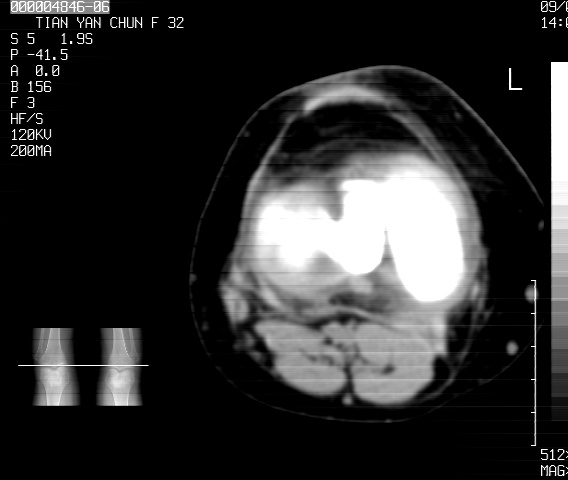

标题: CT18487:请会诊,女32岁,左膝疼痛数日 [打印本页]

标题: CT18487:请会诊,女32岁,左膝疼痛数日

关节面软骨有硬化环考虑退行性变

定位片可见髁间棘骨质增生,支持膝关节退行性变。

定位片可见髁间棘骨质增生,支持膝关节退行性变。建议mri 检查

考虑骨性关节炎